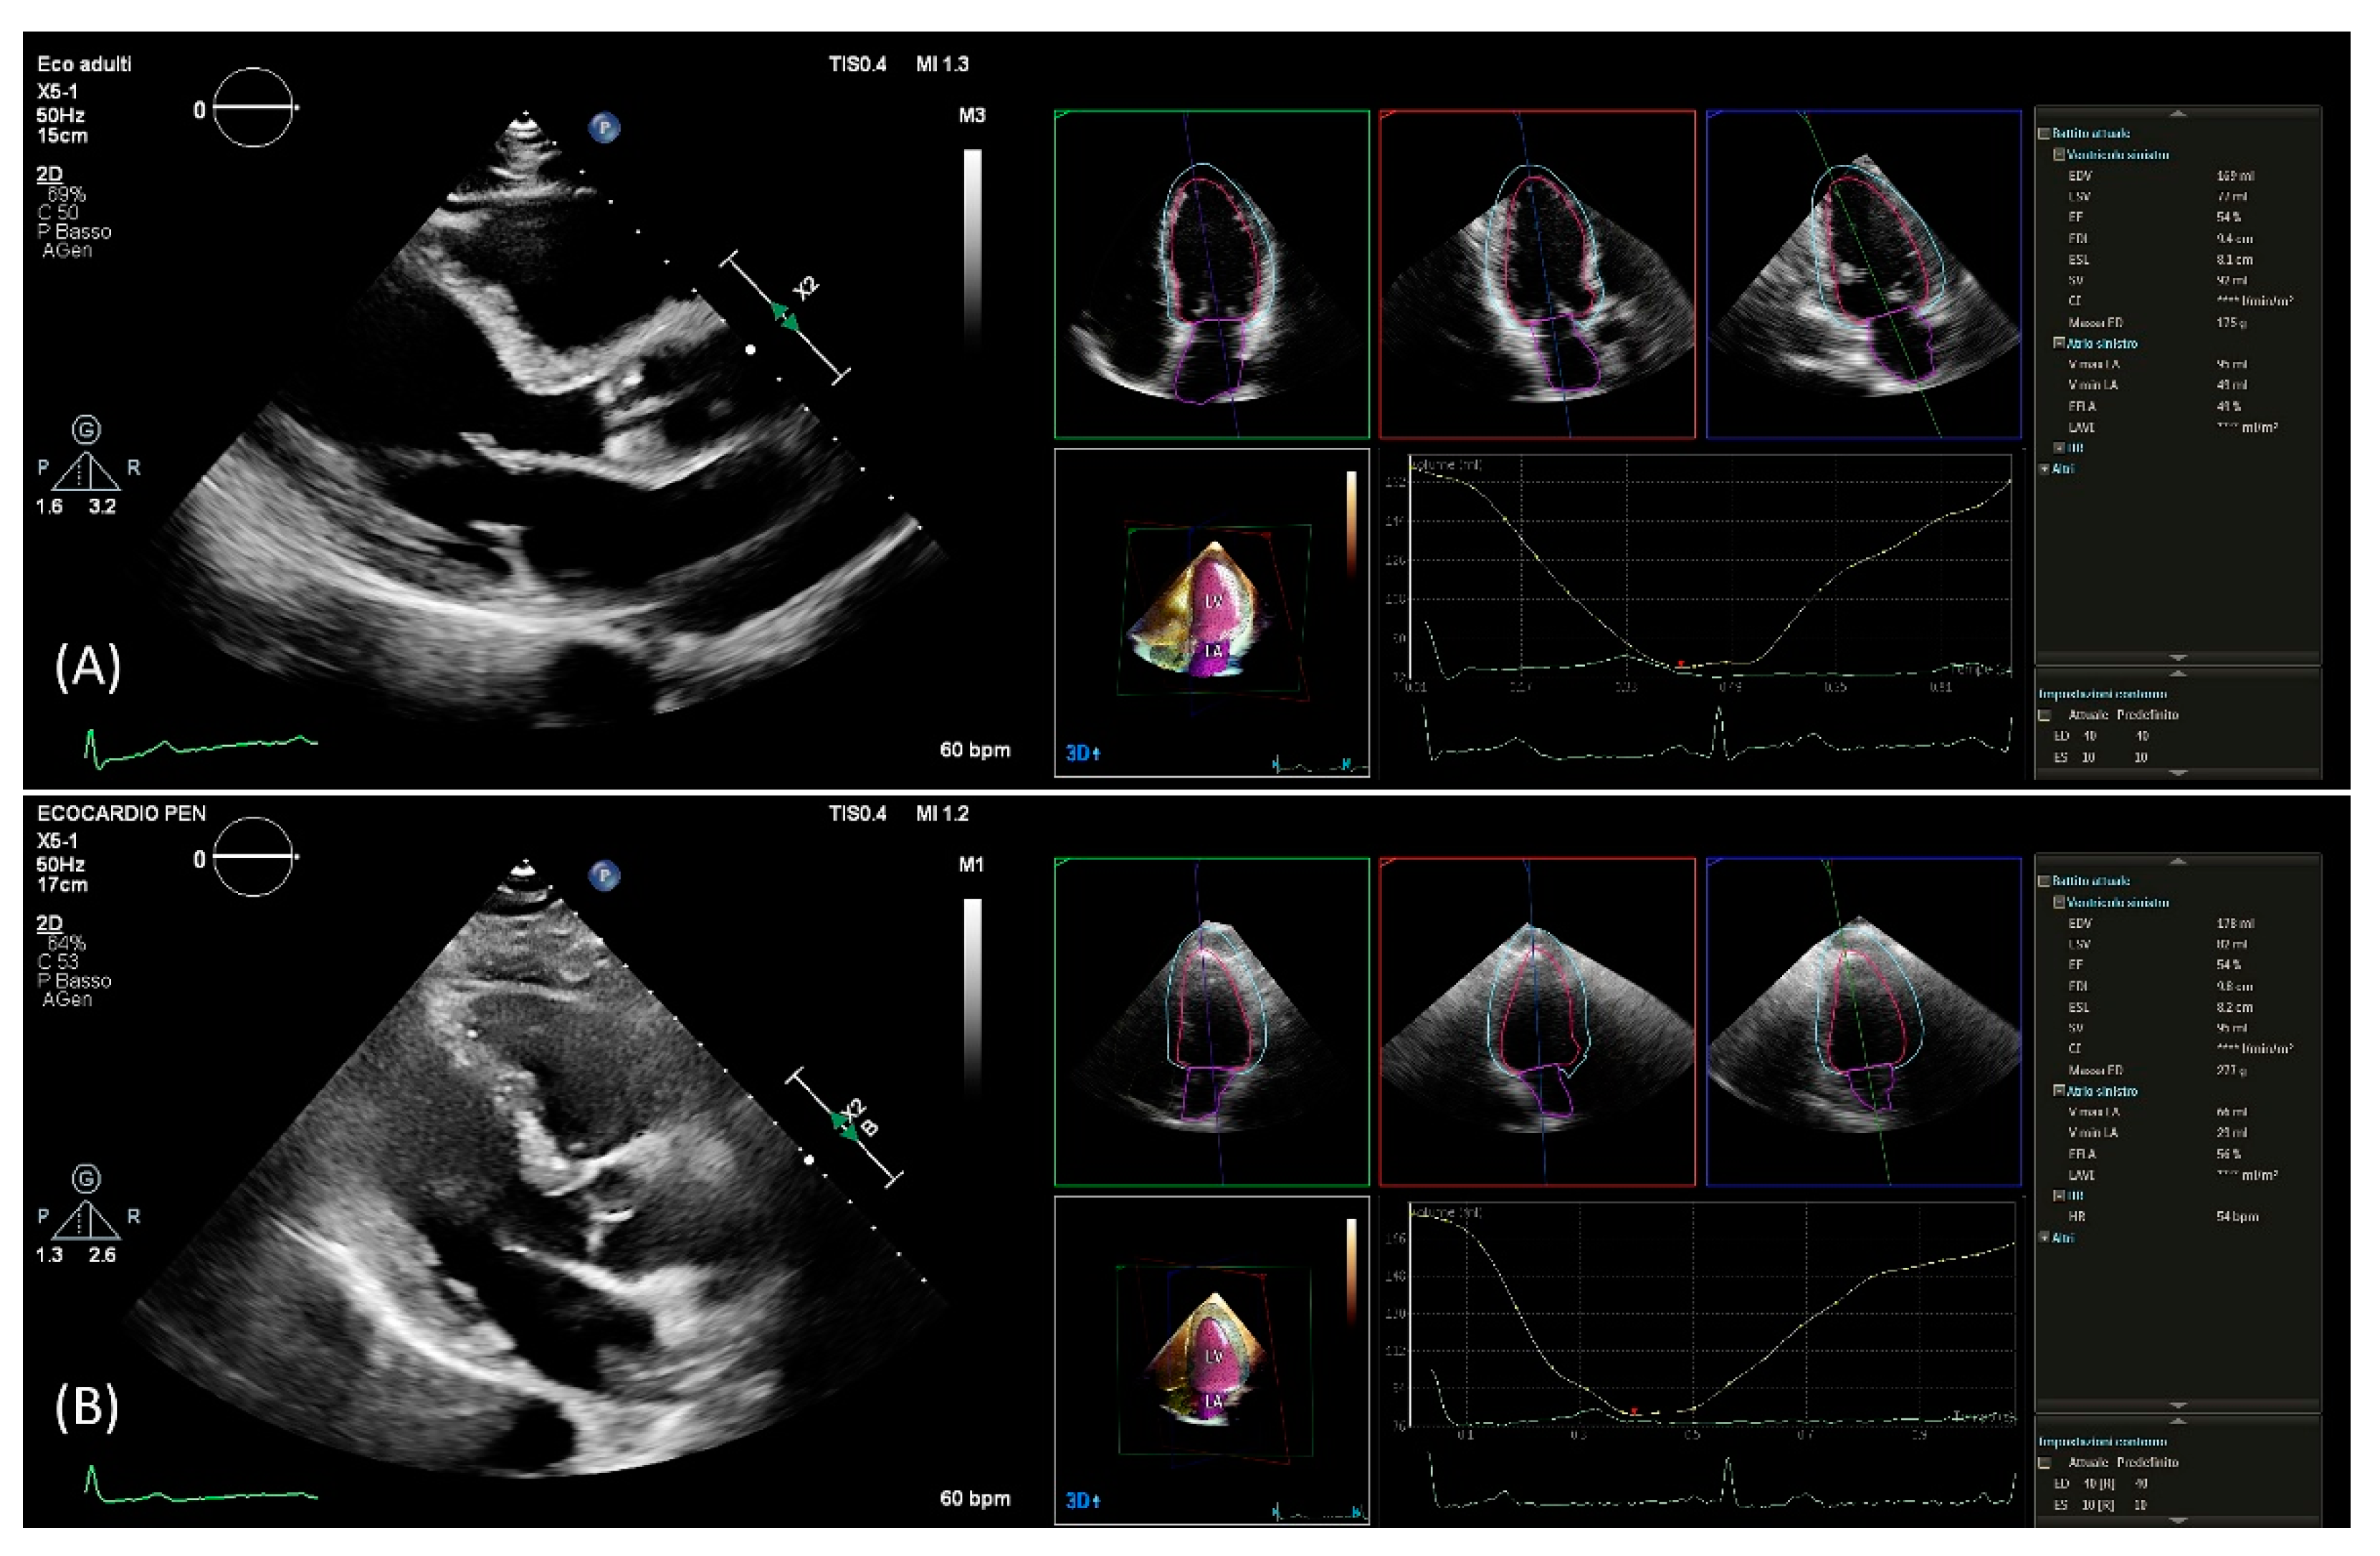

After setting gain, time-gain compensation, and depth on 2D images, a single-beat acquisition mode from the apical 4-chamber view was used to acquire 3D wide-angle datasets. By changing sector width and image depth, the 3D frame rate was optimized. All measurements were performed by the same operator (AB), fully trained in echocardiography with long-standing experience with the 3D technique and trained on echocardiographic datasets with the focus on what constitutes adequate automated analysis. Briefly, the novel vendor software simultaneously detects LV and left atrial endocardial surfaces using an adaptive analytics algorithm, which uses knowledge-based identification to orient and locates cardiac chambers and patient-specific adaptation of endocardial borders from which LV and left atrial volumes are derived directly without geometrical assumptions (Figure 1). LV volumes, left atrial volumes, and ejection fraction were assessed using the 3D method. All measurements were performed online and entered into an electronic database at the time of the echocardiographic study. No modification from the original database was applied, and no measurement was made offline. Hence, the study consisted of a retrospective analysis of data entered into the electronic echocardiographic database.

Figure 1.

PLAX view used for linear 2D measurements and 3D measurements obtained from automated DHM software in a patient with good agreement (A) and in a patient with poor agreement (B) between 2D and 3D mass values. DHM, Dynamic Heart Model; PLAX, parasternal long axis; 2D, two-dimension; 3D, three-dimension.

Using the automated DHM program, which automatically detects LV endo- and epicardial borders at the end-diastole, 3D-LV mass was analyzed, enabling direct LV mass quantification (Figure 1). While it is possible to correct the LV and left atrial endocardial surfaces manually, no changes to the automatically identified cardiac boundaries have been made. Previous studies have shown that LV volumes [8,9,14] and LV mass [12] could be accurately measured using this software, and manual border adjustments led to only clinically insignificant differences. In this study, 3D echocardiography images were analyzed using the same boundary detection sliders for all patients (40 for end-diastole and 10 for end-systole).